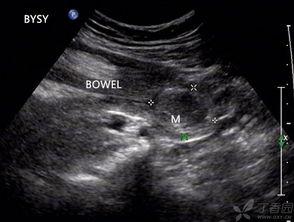

1. 影像学检查:如X光、CT、MRI等,可以清晰地显示肠套叠的情况。